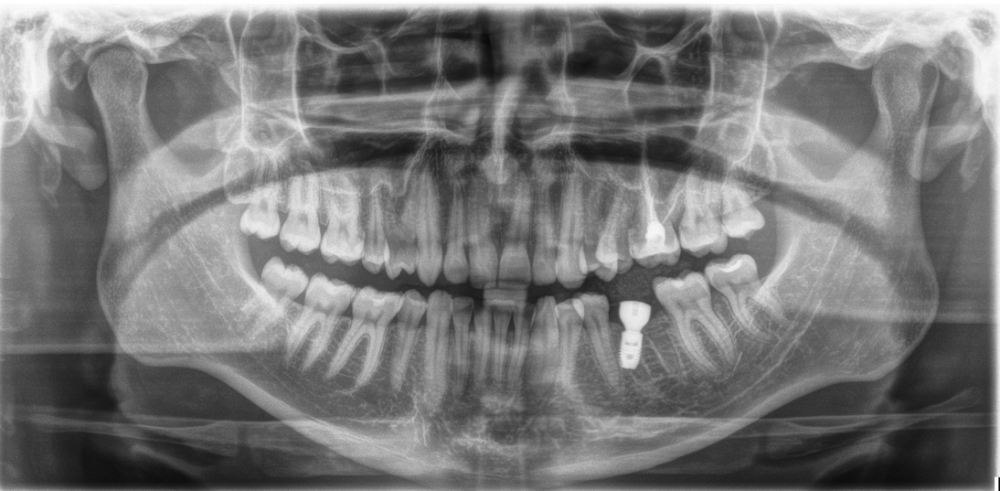

Dimarik12 Опубликовано 11 мая, 2022 Поделиться Опубликовано 11 мая, 2022 (изменено) Здравствуйте! Поставил имплантат вместо удаленной 4 месяца назад нижней шестерки. Мне 26 лет, сделали 3d КТ - костной ткани было достаточно, поэтому костного наращивания не делали. На рентгене после операции зуб, как мне кажется, установлен криво. Нижней левой пятерки не было вовсе у меня (ранее зубы не удаляли, и с детства пятерки не помню снизу). Сделано так, чтобы коронка, установленная в последующем соприкасалась с верхней шестеркой. Подскажите, пожалуйста, такая установка это норма? Какие проблемы могут возникнуть в дальнейшем? Можно ли/нужно ли исправить без изъятия этого импланта, наращивания кости и установки нового? И кажется, что корень импланта задевает или почти задевает корень рядом стоящего. Это может привести к какой патологии? Изменено 11 мая, 2022 пользователем Dimarik12 Ссылка на комментарий

It'sGeorgy Опубликовано 11 мая, 2022 Поделиться Опубликовано 11 мая, 2022 Добрый день. Вам, крайне желательно, показаться ортопеду, который будет протезировать ваш имплантат и задать ему эти вопросы. 1 час назад, Dimarik12 сказал: Подскажите, пожалуйста, такая установка это норма? Какие проблемы могут возникнуть в дальнейшем? Ибо понятие норма - вещь растяжимая. Если бы это был мой винт, я бы его переустановил. 1 час назад, Dimarik12 сказал: И кажется, что корень импланта задевает или почти задевает корень рядом стоящего. Это может привести к какой патологии? Нет. 1 час назад, Dimarik12 сказал: Нижней левой пятерки не было вовсе у меня (ранее зубы не удаляли, и с детства пятерки не помню снизу). Она на месте, прямо перед имплантатом. 1 Ссылка на комментарий